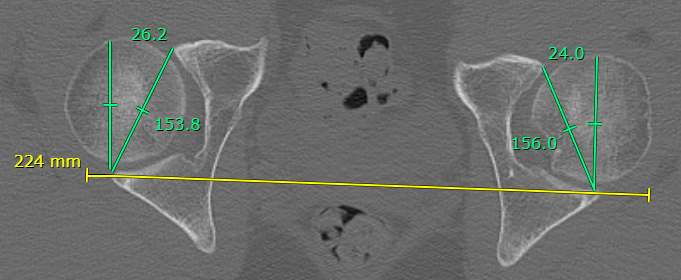

CT / MRI diagnosis

Acetabular version < 15 degrees between B and C

- affected by pelvic tilt and obliquity

- Line A: posterior acetabular walls

- Line B: posterior to anterior acetabular walls

- Line C: perpendicular to line A

Normal acetabular version > 15 degrees

Reduced acetabular version < 15 degrees